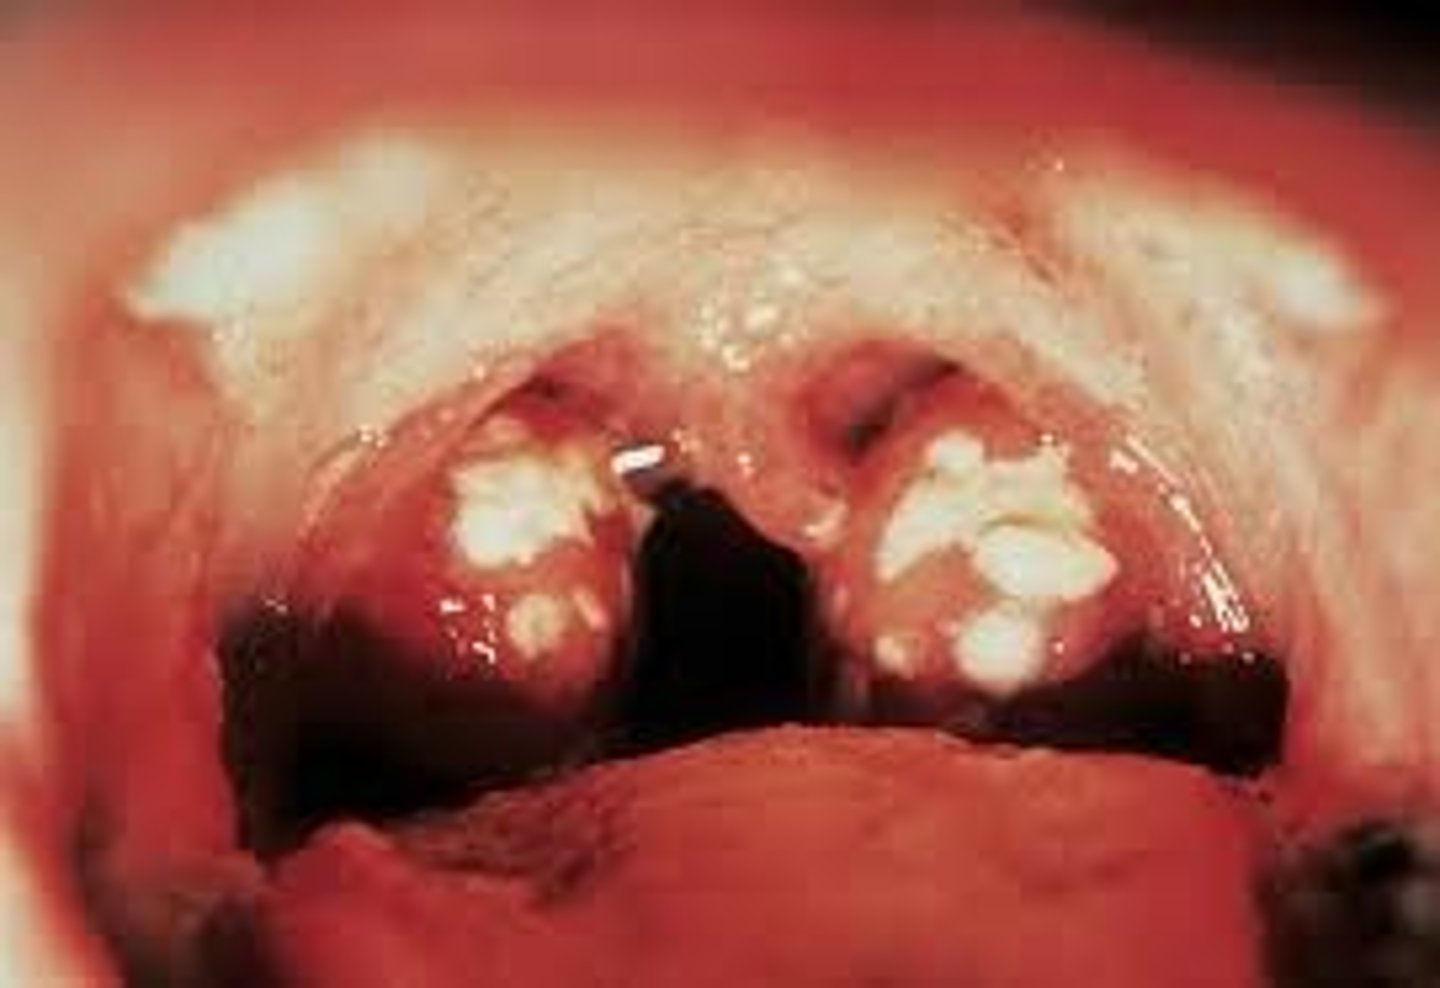

1. A 4-year old child is accompanied by his mother to the emergency room because of high fever and difficulty swallowing. Upon assessment of the mouth and pharynx, the nurse notes that the tongue is strawberry-like, and the tonsils are swollen with yellowish exudates. The uvula is erythematous and there are pinpoint red rashes on the inner cheeks. Which of the following is the priority nursing action?

Ans: (A)

The signs and symptoms exhibited by the client are characteristic of streptococcal pharyngitis, a highly infectious disease. It is appropriate to institute droplet precaution immediately. Informing the physician and providing nourishment and hydration can follow right after.

Feedback: With herpetic stomatitis there is often a low-grade fever with small ulcers covering the mucosa of the mouth. The pain from the ulcers leads to decreased oral intake and even dehydration.